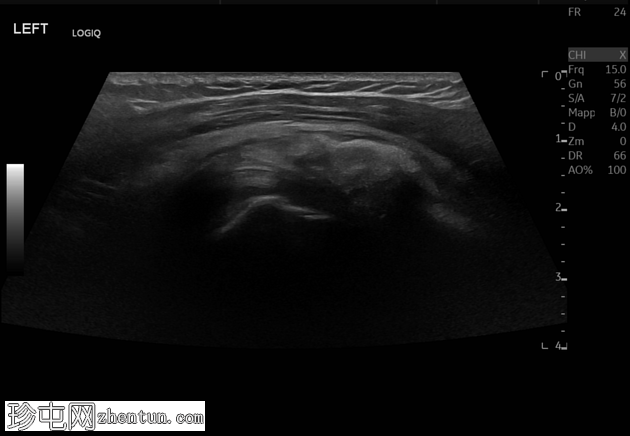

轴位

7.png

肩峰下滑囊-三角肌下滑囊积液内可见轻度高回声、不均匀的钙化灶,无声影(“浆液状钙化”)。滑囊壁增厚,周围脂肪间隙水肿。